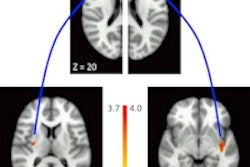

If you are the parent of a preteen child, you know their behavior can sometimes be baffling. So it's interesting that researchers from the University of California, San Francisco used functional MRI (fMRI) to look into why some preteens are more prone to explore than others.

In a study of 62 girls between the ages of 11 and 13, the researchers found that the girls classified as "explorers" based on a behavioral test had a stronger connection between the rostrolateral prefrontal cortex and the posterior insula and putamen regions of the brain on fMRI scans.